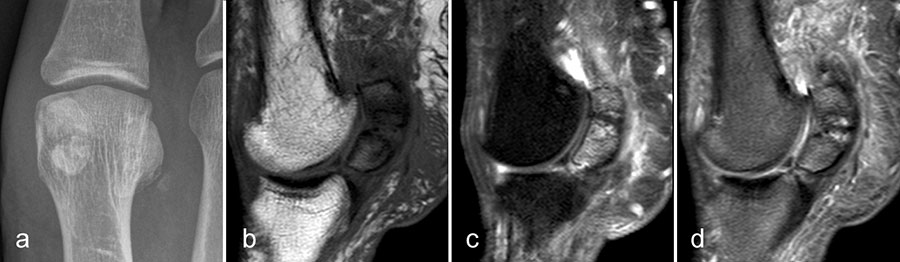

Pathologische Veränderungen der Sesambeine können erhebliche Beschwerden verursachen. Die Unterscheidung einer Fraktur von einem bipartiten Sesambein ist am einfachsten röntgenologisch möglich, da bei einem bipartiten Sesambein die zwei Kerne abgerundet sind und sich nicht wie zwei zusammen passende Puzzlestücke zu einem „ganzen“ Sesambein ergänzen. Findet sich in der MRT ein völlig normales Fettsignal in beiden Anteilen, kann man ebenfalls von einem bipartiten Sesambein ausgehen. Sind ein oder beide Teile in T1 signalgemindert, kann es sich um eine Stressreaktion (Abb. 14) oder auch Nekrose bei vorbestehendem bipartitem Sesambein aber auch um eine Fraktur mit Pseudarthrosenbildung handeln. Die ätiologisch oft unklare entzündliche Aktivierung eines Sesambeins wird als „Sesamoiditis“ bezeichnet 67.

Typische Gichtmanifestation an der Großzehe mit Tophusstachel (Pfeil) und großem Tophus, in welchem Uratablagerungen identifiziert werden können (Pfeilspitze). T1-gewichtete Sequenz vor (a) und nach (b) Kontrastmittelgabe, letztere mit Fettsuppression.

Dies erst recht, wenn diese Arthritis am Großzehen­grundgelenk auftritt (Abb. 15). In diesen Fällen sollte man den Verdacht auch dann aufrechterhalten, wenn die MRT nur eine unspezifische Entzündung zeigt und die Harnsäurewerte, die starken Schwankungen unterliegen können, nicht erhöht sind.

Spezifische MR Befunde finden sich erst bei der chronischen Gicht, wenn sich in T2 sehr signalarme Kristallablagerungen und Gicht-Tophi bilden. Letztere führen dann häufig zu den aus der Röntgendiagnostik bekannten gelenkfernen Erosionen.

Abbildung 15: Typische Gichtmanifestation an der Großzehe mit Tophusstachel (Pfeil) und großem Tophus, in welchem Uratablagerungen identifiziert werden können (Pfeilspitze). T1-gewichtete Sequenz vor (a) und nach (b) Kontrastmittelgabe, letztere mit Fettsuppression.